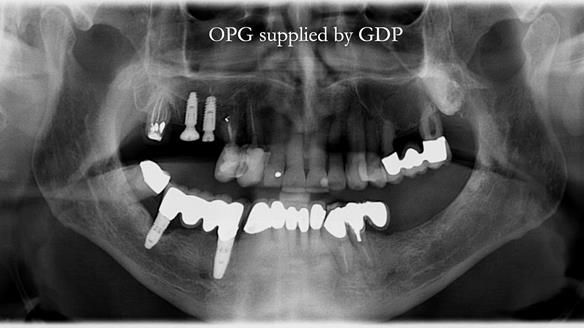

I first met Ken in 2015, when he was 80 years old.

He had lived in both the UK and the USA, spending many years in Florida, where he received extensive dental and periodontal care.

Like an increasing number of patients I now see (around 35% of referrals), Ken had implants that were failing or had already failed.

The starting point

We began with the lower jaw.

A posterior implant 47 had lost integration and was infected. This was removed.

Ken did not want further implant surgery.

Instead, we made a Scandinavian-style, metal-based lower RPD.